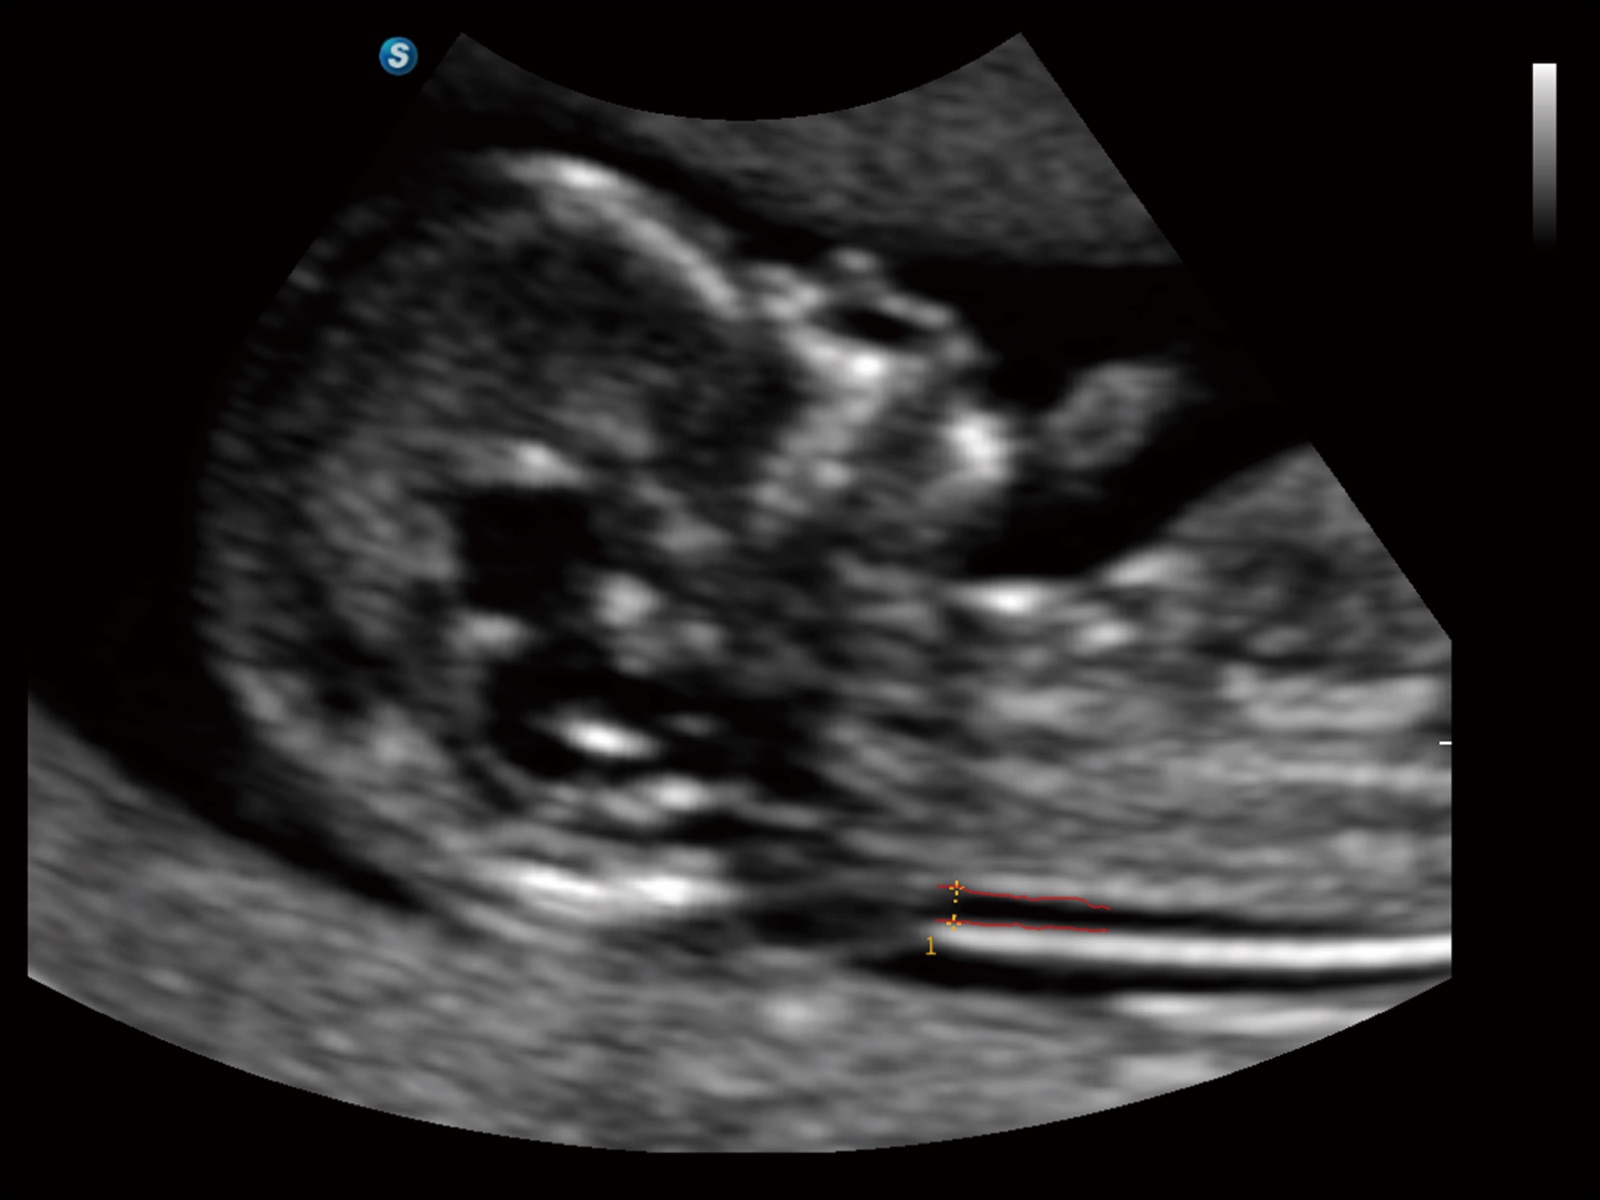

妇产应用